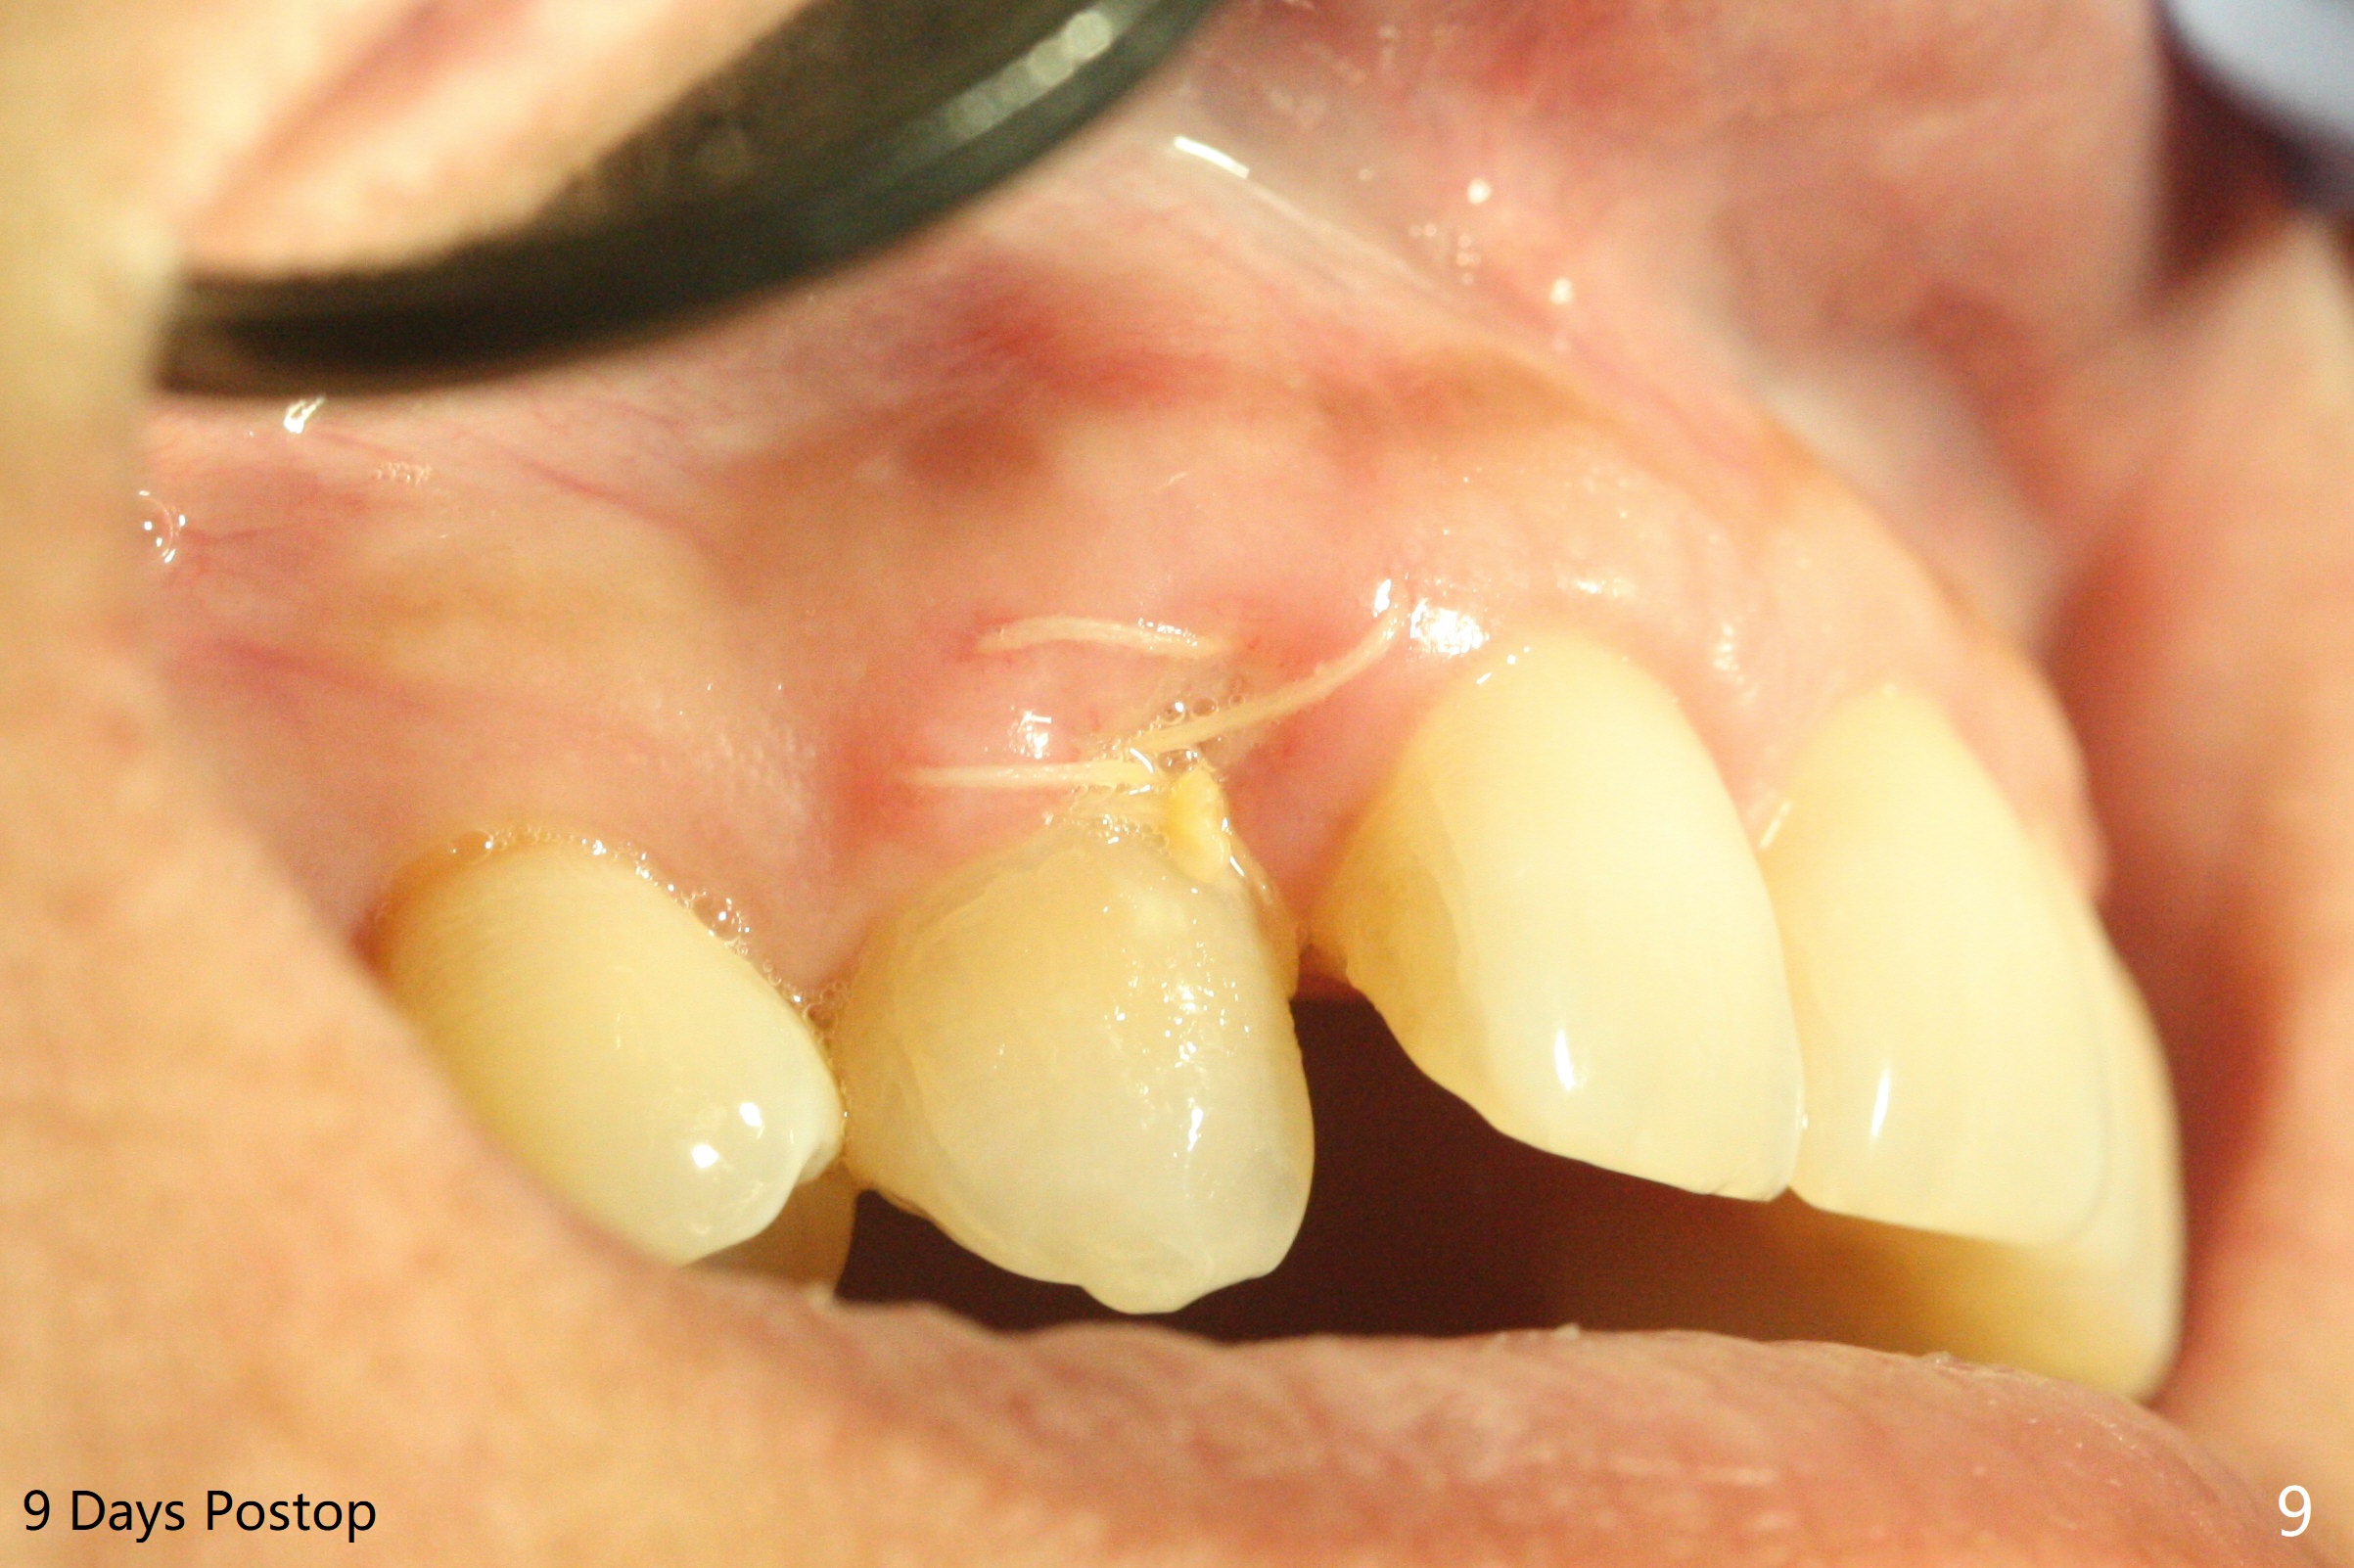

A 54-year-old woman seeks treatment for the tender upper right lateral incisor (Fig.1-4: 2 because of palatal cervical caries (Fig.3 <) and periapical radiolucency (*)), which overlaps with the palatal canine (3). One of treatment options is to extract the lateral and to orthodontically move the canine to the position of the lateral, particularly the root (Fig.5 arrow). When the lateral is removed, the labial bone of the canine is thin (Fig.6). Allograft is placed (Fig.8 * and dashed line), covered with Amnion-Chorion Allograft (Bioxclude) and sutured with 4-0 PGA (Fig.7). The wound heals 9 days postop (Fig.9,10). The patient is grateful because of no pain, which she thinks is due to bone graft, whereas Amnion-Chorion membrane is another contributory factor. The lateral root convexity remains 1 month postop (Fig.11 *); she is undecided upon orthodontic treatment.